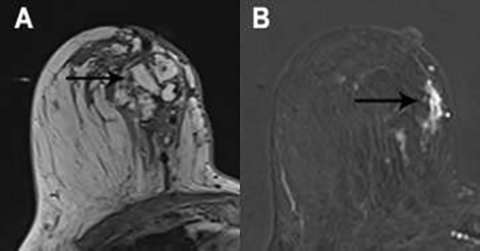

Fat necrosis has a variable imaging appearance, with many cases requiring follow-up imaging (BI-RADS 3) or biopsy (BI-RADS 4).2 Internal fat signal intensity is a classic imaging feature (Figure 3a). Enhancement is variable and may be rim, focal, or diffuse (Figure 3b).3 Calcifications may be seen as signal voids. Correlation with mammography is helpful in identifying central fat density as well as the typical calcifications seen in fat necrosis.